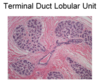

This image is an example of what anatomical structure in the breast?

The Terminal Duct - Lobular Unit